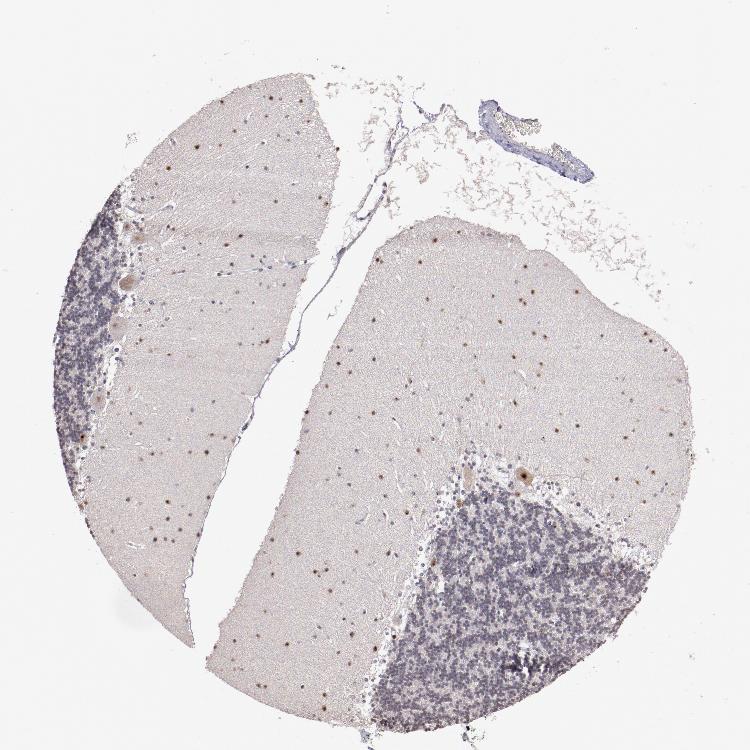

CEREBELLUM - Antibody stainingi

Antibody staining in the annotated cell types in the current human tissue is reported as not detected, low, medium, or high, based on conventional immunohistochemistry profiling in selected tissues. This score is based on the combination of the staining intensity and fraction of stained cells.

Each image is clickable and will lead to virtual microscopy that enables deeper exploration of all samples and also displays staining intensity scores, fraction scores and subcellular localization as well as patient and tissue information for each sample.

Antibody HPA002554

Purkinje cells Medium

Cells in granular layer Medium

Cells in molecular layer Medium